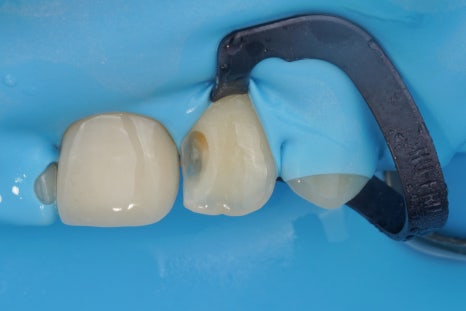

그리고 이렇게 하기 위해서는

러버댐이라는 재료를 잘 써야 해요.

러버댐을 잘 쓰는 것이

가장 중요한 첫단계입니다.

러버댐이라는 재료는

그냥 썼다고해서 다 된 게 아니라

그 목적을 이루기 위해 필요한 여러 원칙들을

하나하나 지켜야만

원하는 결과를 얻을 수 있겠죠.

어금니, 앞니 가릴 것 없이

중요한 접착의 순간에

이렇게 러버댐을 사용하는 것,

그래서 구강 내에 있는

뺨과 혀,

피와 침과 습기로부터

치아를 완전히 격리하고 방습하는 것.

그것이 교과서에 적힌 원칙이고

결과를 High-end로 유지할 수 있는

비결입니다.